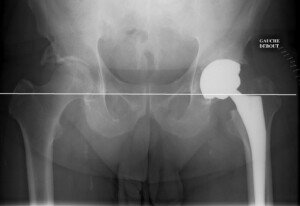

Clinicaccess vous propose des services de haute qualité en matière de chirurgie orthopédique maroc, notamment l’intervention chirurgicale qui vous permet la pose d’une prothèse de la hanche totale qui constitue le remplacement définitif des malheureux cartilages qui ont connu une forte dégradation à cause de l’âge ou bien d’un accident grave au passé. Clinicaccess vous garantit des soins bien établis et appropriés à votre situation, après l’intervention vous serez levés dès le deuxième jour postopératoire par notre kinésithérapeute et les pansements de la cicatrice sont installés une fois tous les quatre jours, vous pouvez même ressortir de la clinique au cinquième jour de votre hospitalisation pour entamer tranquillement votre processus de convalescence. Clinicaccess c’est des solutions efficaces et durables pour vos pépins de santé quel qu’ils soient !